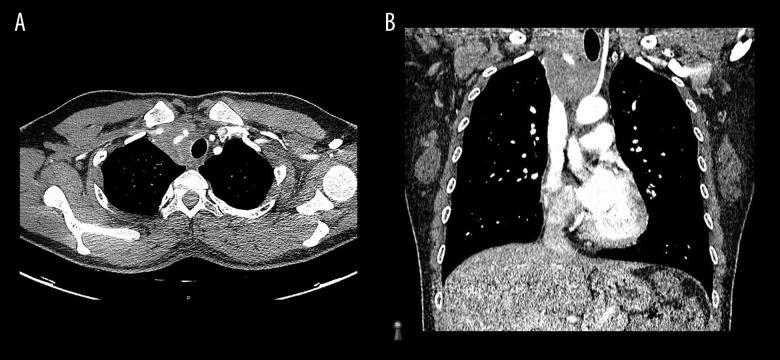

BACKGROUND Fibrosing mediastinitis is a rarely seen, progressive disease. It results from an excessive fibrotic reaction in the mediastinum. We describe a presentation of fibrosing mediastinitis that, to our knowledge, has never been seen before. CASE REPORT A 30-year-old female Colombian flight attendant presented with a right eyelid droop. Examination revealed partial right-sided ptosis and miosis but no anhidrosis. An ill-defined firm swelling was palpable at the root of the neck. Chest radiography revealed a widened mediastinum, and computerized tomography (CT) showed a right paratracheal mass without calcification extending to the thoracic inlet, encasing multiple blood vessels. All basic blood tests, magnetic resonance imaging of the head, and ultrasound Doppler of the neck vessels were normal. History and work up for infections including fungal diseases, granulomatous diseases, vasculitis, and autoimmune diseases were negative. Positron emission tomography (PET) showed significant FDG uptake in the mediastinum. Mediastinal biopsy was histologically consistent with fibrosing mediastinitis. All relevant immunohistochemistry and microbiological studies were negative. Subsequently, the patient developed signs of superior vena cava compression; this was managed by balloon angioplasty, which resulted in improvement of symptoms. However, over time, her symptoms worsened progressively, resulting in a left-sided ptosis and radiological progression of the mass on CT. She received treatment with rituximab and concomitant steroids, which yielded excellent results: the treatment led to both resolution of her symptoms and regression of the mass and its metabolic activity on PET scan. CONCLUSIONS Fibrosing mediastinitis can present with an incomplete Horner's syndrome. Treatment with rituximab and steroids shows promising results in select cases of metabolically active idiopathic fibrosing mediastinitis.

一名 30 岁的哥伦比亚空姐出现右侧眼睑下垂。检查发现右侧部分上睑下垂和瞳孔缩小,但无无汗。颈部根部可触及一界限不清的坚硬肿胀。胸部 X 线摄影显示纵隔增宽,计算机断层扫描(CT)显示右侧气管旁肿块,无钙化,延伸至胸入口,包绕多个血管。所有基本血液检查、头部磁共振成像和颈部血管超声多普勒均正常。感染史和检查(包括真菌感染、肉芽肿性疾病、血管炎和自身免疫性疾病)均为阴性。正电子发射断层扫描(PET)显示纵隔内 FDG 摄取明显。纵隔活检组织学符合纤维性纵隔炎。所有相关的免疫组织化学和微生物学研究均为阴性。随后,患者出现上腔静脉压迫的迹象,通过球囊血管成形术进行治疗,症状得到改善。然而,随着时间的推移,她的症状逐渐恶化,导致左侧上睑下垂和 CT 上肿块的影像学进展。她接受了利妥昔单抗和皮质类固醇治疗,效果非常好:治疗不仅缓解了她的症状,还使肿块及其代谢活性在 PET 扫描上消退。